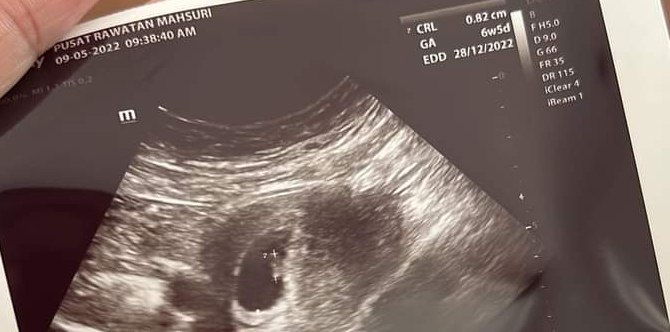

Setelah sekian lama penantian, akhirnya Puan Ayda Bella Jamal telah pun disahkan hamil.

Berkongsi kegembiraan di laman Facebook mengenai kehamilannya itu, Puan Ayda turut berkongsi cara ikhtiar hamil yang dilakukan sepanjang tempoh perkahwinannya.